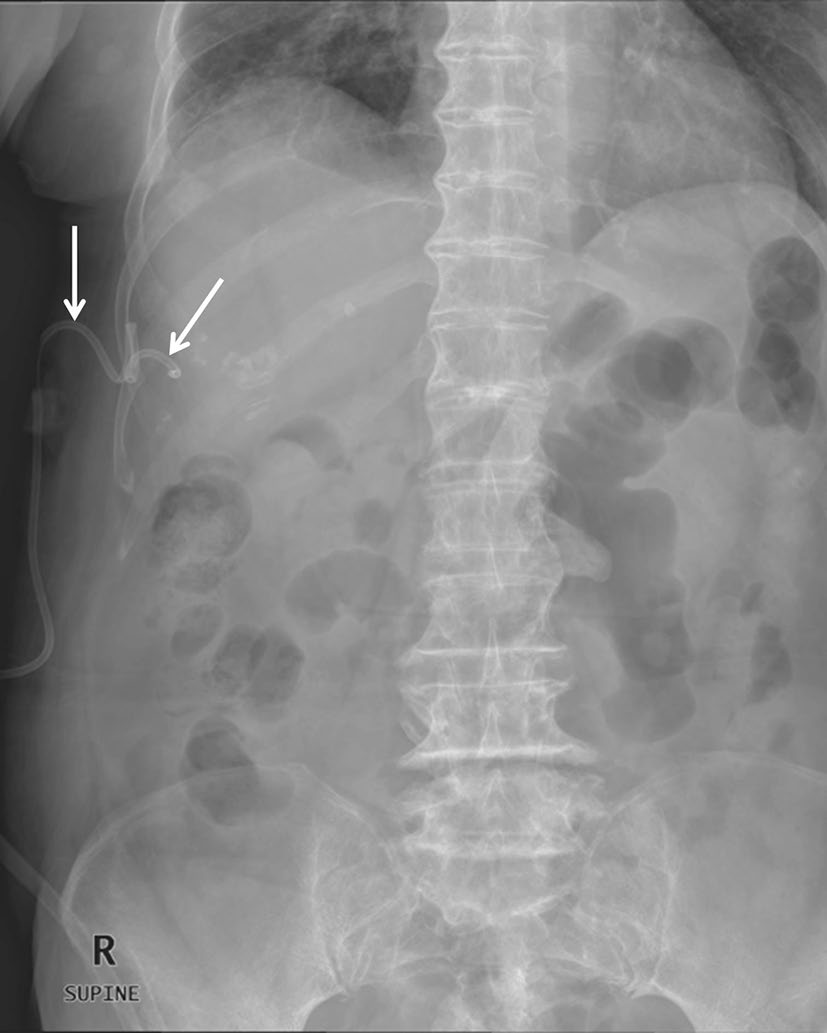

出血

出血可能发生在医疗设备安装期间或移除后不久。大多数腹壁轻微出血可通过压迫处理[14]。然而,一些难治性出血和腹腔内活动性出血的情况仍然是最严重的并发症,需要进行栓塞或手术干预。仅靠腹部X光片无法检测到出血。需使用对比增强多探测器CT是检测出血的一种准确的诊断方法(图22)。